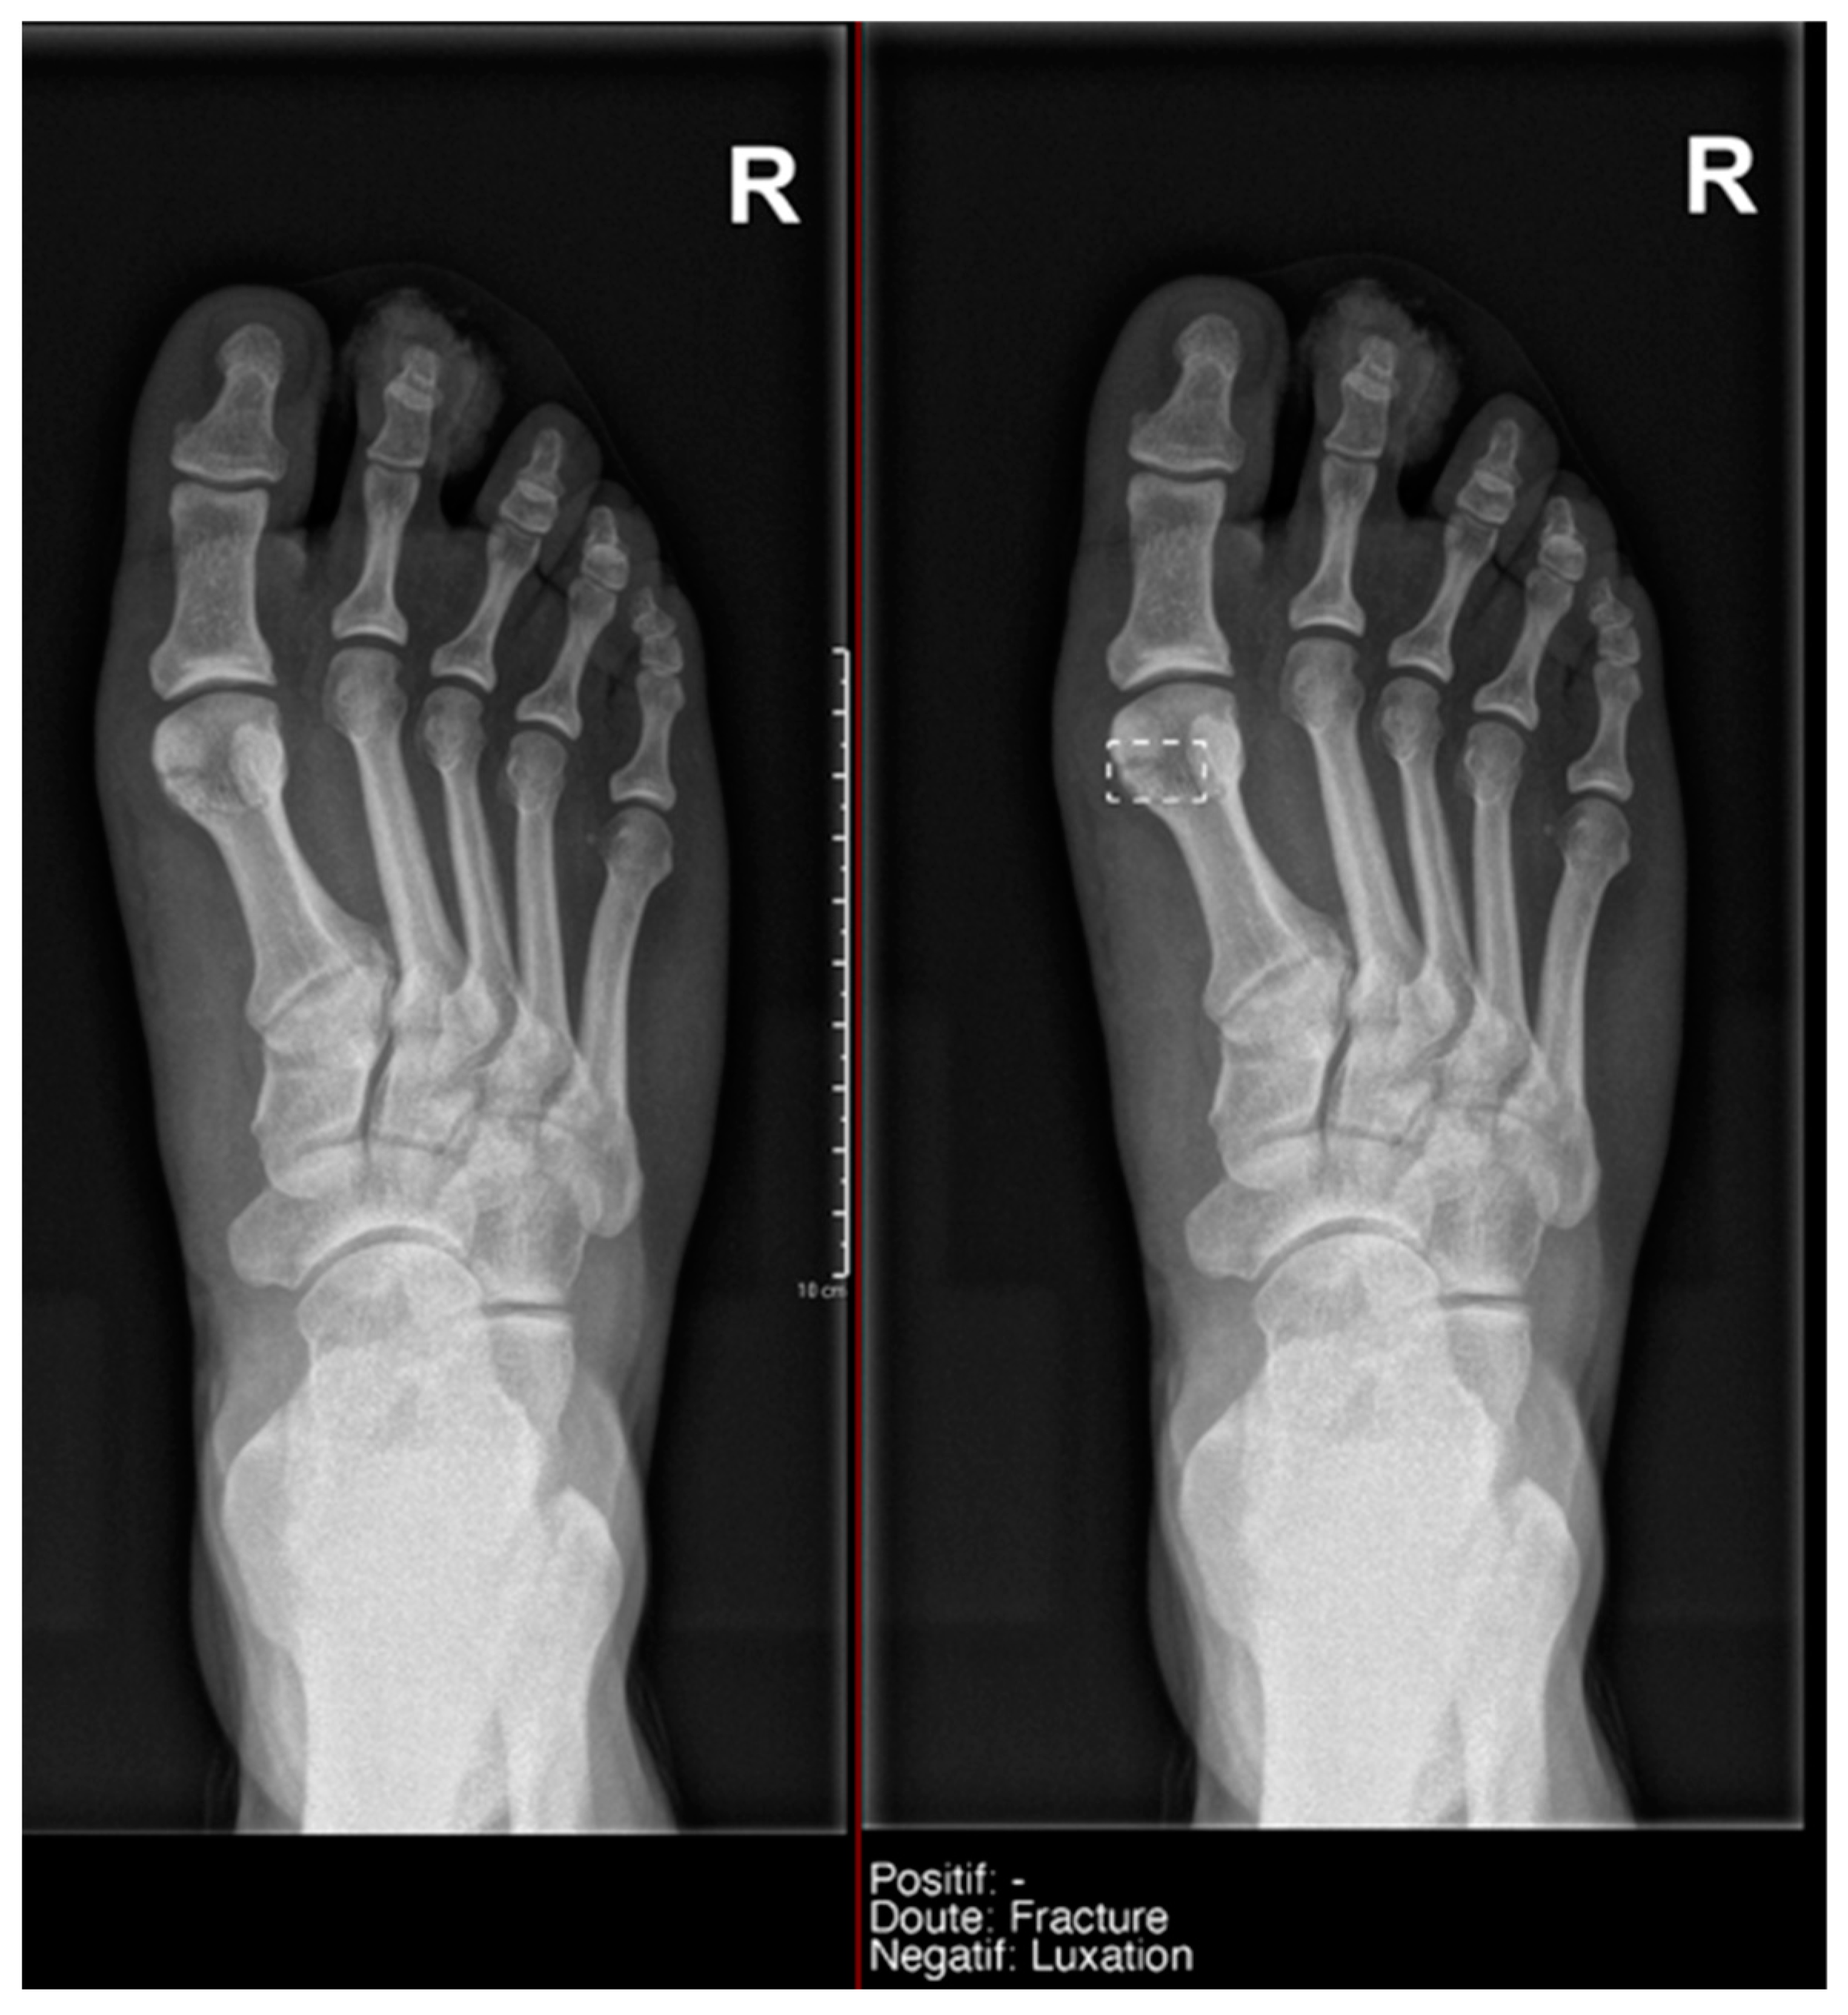

This difference in the positivity of cases marked as doubtful was influenced by the presence of anatomical variants in the following:

- Ankle and foot: On six occasions, Milvue marked the fracture variable as doubtful in cases with a bipartite medial sesamoid (two patients), an accessory sesamoid at the base of the 5th metatarsal, synphalangism, os peroneum, and os naviculare. (Figure 8).

Figure 8. Example of an anatomical variant (bipartite hallux sesamoid), which was recorded as doubt fracture by AI and as negative by the radiology resident. - Hand: Milvue marked the fracture variable as doubtful in the case of multiple accessory ossicles.